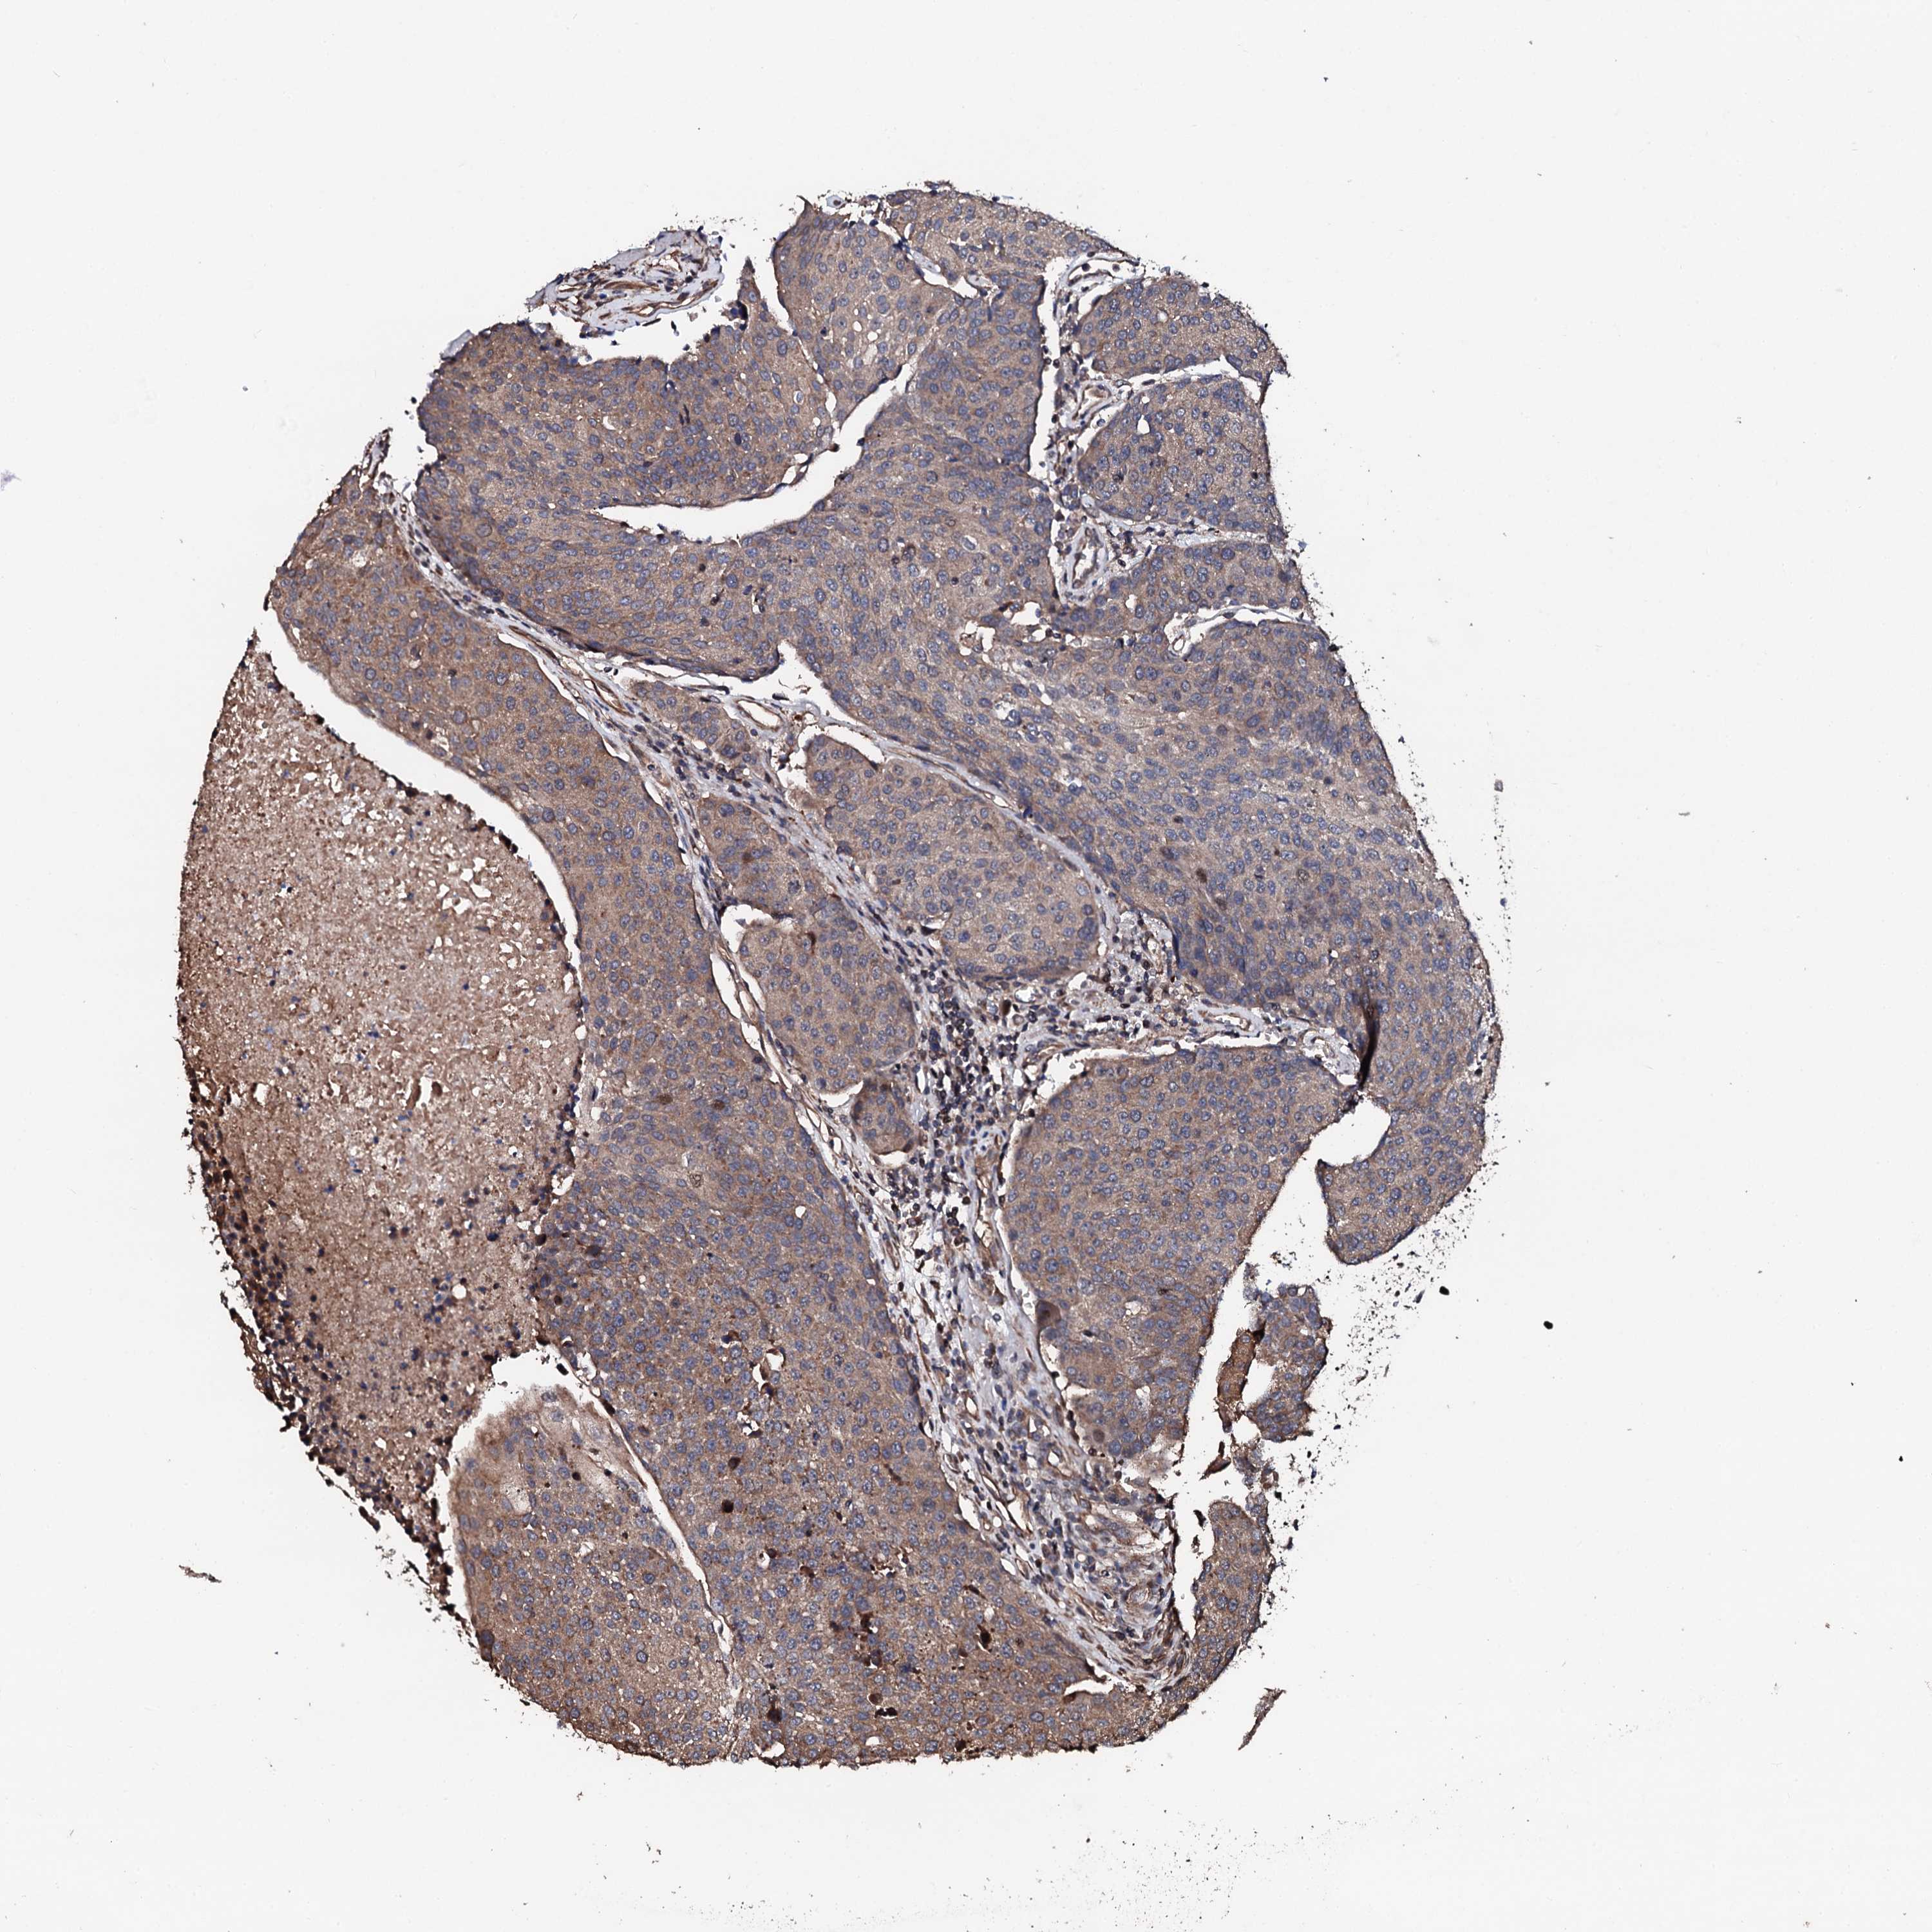

UROTHELIAL CANCER - Protein expressioni

A mouse-over function shows sample information and annotation data. Click on an image to view it in a full screen mode. Samples can be filtered based on level of antibody staining by selecting one or several of the following categories: high, medium, low and not detected. The assay and annotation is described here.

Note that samples used for immunohistochemistry by the Human Protein Atlas do not correspond to samples in the TCGA dataset.

Antibody stainingi

Antibody staining in the annotated cell types in the current human tissue is reported as not detected, low, medium, or high, based on conventional immunohistochemistry profiling in selected tissues. This score is based on the combination of the staining intensity and fraction of stained cells.

Each image is clickable and will lead to virtual microscopy that enables deeper exploration of all samples and also displays staining intensity scores, fraction scores and subcellular localization as well as patient and tissue information for each sample.

Antibody HPA039377

Antibody HPA040375

Urothelial carcinoma, High grade

Urothelial carcinoma, Low grade